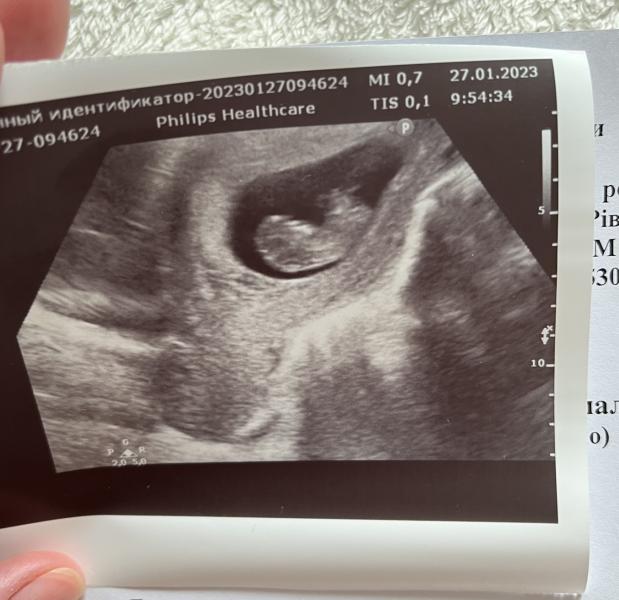

Була сьогодні на узд🥰 побачила нашу крихітку❤️ 10,5 тижнів🤩 дуже активна/ий

Але потрібно бути більш обережною зараз… тонус матки, сильні болі в животі, і виділенні ті що не потрібно… токсикоз поки нікуди не планує відступати😅 надіюся що все буде добре!